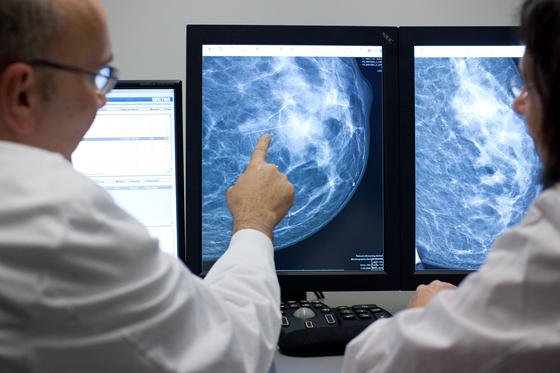

Das Metall wirkt nämlich auch als Kontrastmittel bei Röntgenaufnahmen, mit denen der Behandlungsfortschritt kontrolliert wird. Das Flüssigmetall reagiert mit der sauren Umgebung innerhalb des Tumors. Dabei werden Gallium-Ionen frei, die die die Wirkung des Medikaments noch erhöhen.